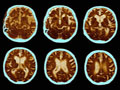

While Alzheimer’s disease is most common in people over the age of 65, it can strike adults of any age irrespective of their gender, background or socioeconomic status. According to the Alzheimer’s Association, an estimated 5.3 million Americans are currently living with Alzheimer’s disease. The number of Americans aged 65 and over with Alzheimer’s is estimated to reach 7.7 million in 2030. By 2050, between 11 million and 16 million Americans over 65 are expected to have Alzheimer’s disease.